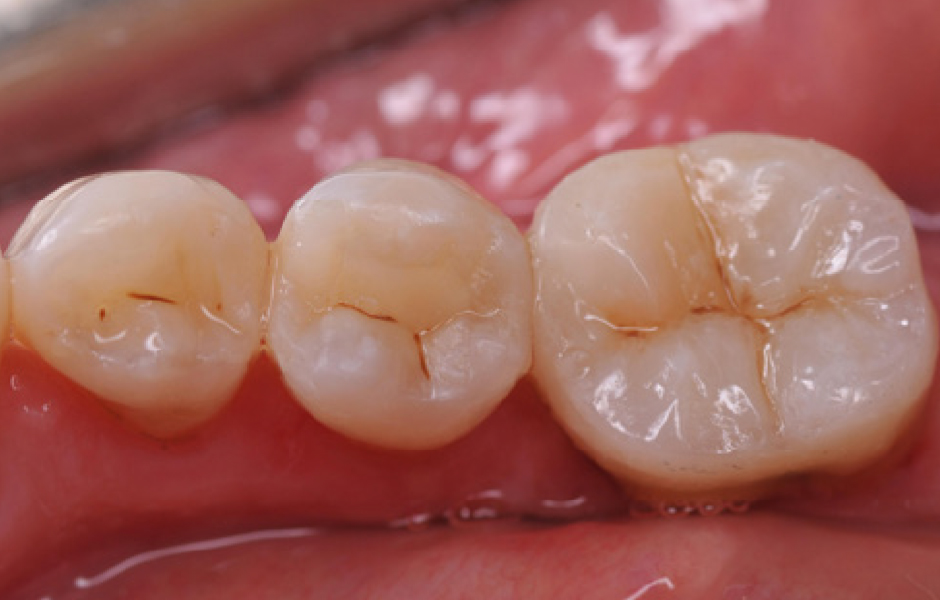

Obr. 5: Přímé výplně. Za dodržení zásad adhezivního postupu byly dokončeny přímé výplně na premolárech s použitím jednoho odstínu SimpliShade Bulk Fill (Kerr) a následně provedena individualizace okluze hnědými pigmenty. Díky snadné manipulaci a nízkému polymeračnímu smrštění bylo možné vyplnit obě kavity jedinou 4mm vrstvou kompozitu. Materiál byl přizpůsoben kavitě a modelován pomocí techniky Espresso posterior lines, což ušetřilo cenný čas.